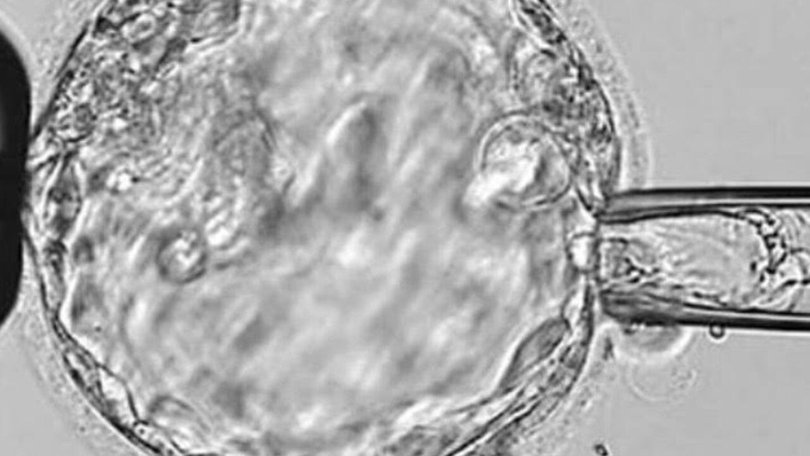

An Australian fertility giant has issued a major update after it was rocked by a shocking embryo bungle at two of its clinics in Queensland and Victoria.

Fertility treatment company Monash IVF has agreed to settle with families that were impacted by embryo bungles at two of its clinics.

The incident came after a separate error at a Brisbane clinic in 2023, when staff mistakenly implanted the wrong embryo into a patient, resulting in a woman giving birth to another couple’s child.